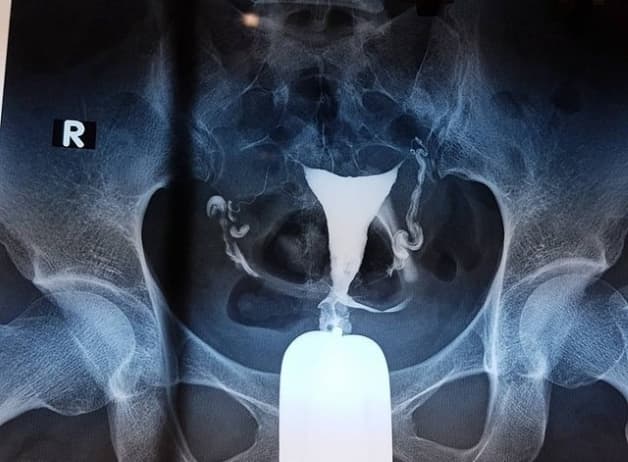

2.1 Chụp cản quang với vòi trứng

Thời điểm tốt và phù hợp nhất để tiến hành chụp cảng quang vòi trứng đó là sau khi người bệnh sạch kinh từ 2-3 ngày. Sau khi tiến hành kiểm tra và vệ sinh sạch sẽ âm đạo cũng như tử cung thì các bác sĩ sẽ tiến hành bơm vào buồng tử cung một ít dung dịch có chứa chất cản quang rồi chụp X-quang. Từ kết quả được hiển thị trên phim chụp thì các bác sĩ sẽ có căn cứ để kết luận xem bạn có bị tắc vòi trứng hay không.

Phương pháp này có ưu điểm đó là xác định được ống dẫn trứng, vòi trứng có thông suốt hay không, đồng thời cũng xác nhận xem buồng tử cung có điều gì bất thường hay không. Tuy nhiên, điểm hạn chế của phương này đó là khó quan sát được những tổn thương bên ngoài vòi trứng cũng như là niêm mạc ở vòi trứng. Đôi khi phương pháp này không cho ra kết quả chính xác bởi chất cản quang gây co thắt vòi trứng.

Không áp dụng thực hiện phương pháp này đối với những người phụ nghi ngờ hoặc có thai, những người bị dị ứng với chất cản quang hay những người bị chảy máu âm đạo.

Chụp cản quang với vòi trứng giúp xác định được ống dẫn trứng, vòi trứng có thông suốt hay không